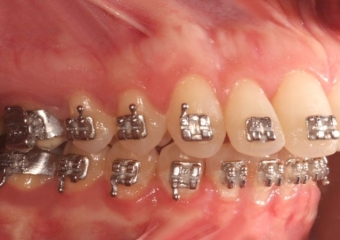

Mordida final